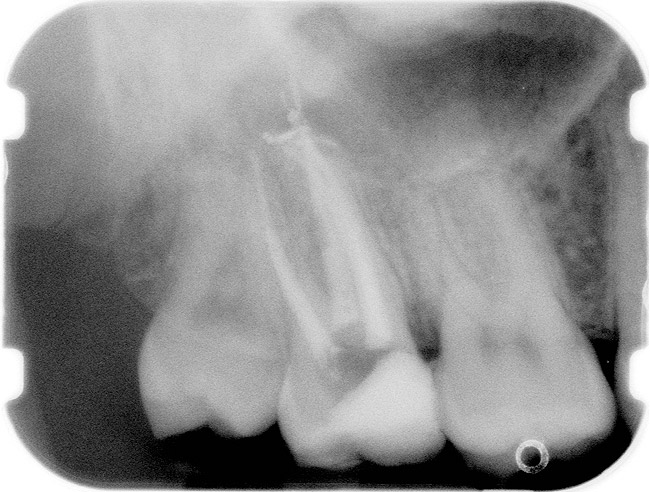

A Class IN maxillary bicuspid was previously restored with a fiber post and an all-porcelain crown (Figure 1). The forces of the oral environment resulted in fracture of the fiber post and crown failure. The remaining fiber post in the root was removed, and anti-rotational areas were prepared for a cast post (Figure 2). A gold cast post was constructed at a dental laboratory, using an indirect technique (Figure 3). A porcelain-fused-to-metal (PFM) crown was constructed with a bevel finish to provide a ferrule and reduce forces on the post (Figure 4 and Figure 5).

Figure 1  X-ray of an endodontically treated second bicuspid restored with a fiber post, core, and all-porcelain crown.

Figure 1